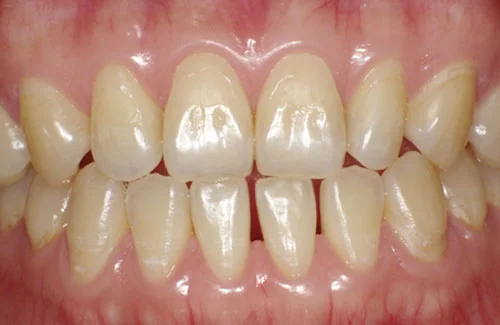

<症例3>前歯のクロスバイトでお悩み

右上の前歯2本が反対に咬合している、いわゆるクロスバイトが主訴でご来院なさいました。

主訴以外の部分には大きな叢生はなく、また患者様も装着時間をしっかり守ってくださったので約6ヶ月で改善することができました。

患者様と症状

主訴:上の前歯が出ている

性別・年齢:20代女性

問題点:上顎左側側切歯のクロスバイト、叢生

診断:前歯部の叢生を伴うアングルⅠ級の不正咬合

主なリスク:矯正中一時的に咬合しにくくなる、歯肉退縮

症状:叢生(そうせい) 上顎前突(じょうがくぜんとつ)

治療内容

治療期間:6ヶ月

治療費用:495,000円(税込)

プラン:14枚コース/ライトプラン

抜歯:親知らずのみ抜歯

再診治療費:無し

追加治療費:無し

保定装置費:無し

治療前後の写真

・2本の前歯が前突しておりましたが、矯正で自然な歯並びになりました。

・前歯の1本が下の歯の裏側に噛み合うクロスバイトになっていましたが、矯正で改善されました。